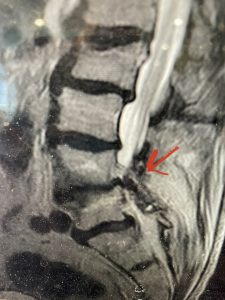

This 57 year-old male had a long history of low back pain and left lower extremity pain and numbness. The patient had failed conservative treatment of physical therapy and epidurals. MRI revealed tight left L2-3 and L3-4 lateral recess stenosis as well as significant right L4-5 facet arthropathy and right lateral recess stenosis as well as a grade 1 L4-5 spondylolisthesis

(Fig 2) Sagittal T2-weighted lumbar MRI demonstrating (arrow) tight lateral recess stenosis